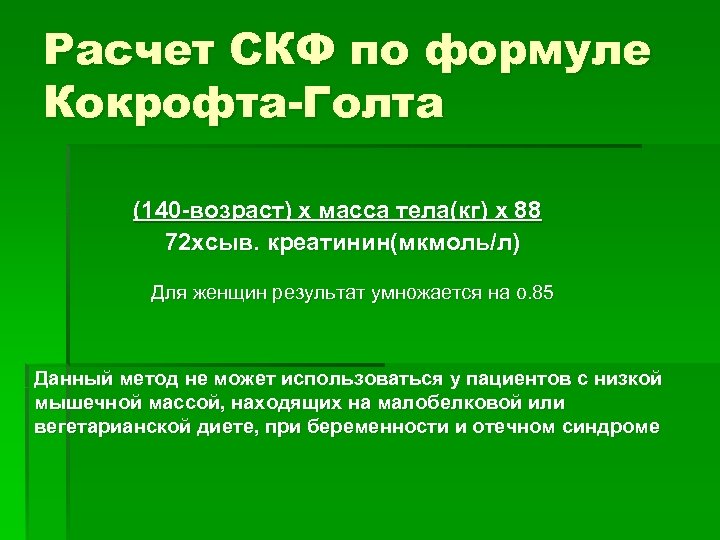

Расчет СКФ по формуле Кокрофта-Голта (140 -возраст) х масса тела(кг) х 88 72 хсыв. креатинин(мкмоль/л) Для женщин результат умножается на о. 85 Данный метод не может использоваться у пациентов с низкой мышечной массой, находящих на малобелковой или вегетарианской диете, при беременности и отечном синдроме